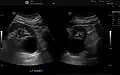

Renal ultrasonography of a simple renal cyst with posterior enhancement. -

Renal cyst as seen on abdominal ultrasound -